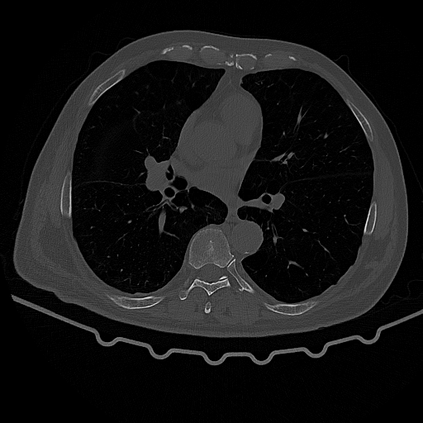

CT reconstruction provides radiologists with images for diagnosis and treatment, yet current deep learning methods are typically limited to specific anatomies and datasets, hindering generalization ability to unseen anatomies and lesions. To address this, we introduce the Multi-Organ medical image REconstruction (MORE) dataset, comprising CT scans across 9 diverse anatomies with 15 lesion types. This dataset serves two key purposes: (1) enabling robust training of deep learning models on extensive, heterogeneous data, and (2) facilitating rigorous evaluation of model generalization for CT reconstruction. We further establish a strong baseline solution that outperforms prior approaches under these challenging conditions. Our results demonstrate that: (1) a comprehensive dataset helps improve the generalization capability of models, and (2) optimization-based methods offer enhanced robustness for unseen anatomies. The MORE dataset is freely accessible under CC-BY-NC 4.0 at our project page https://more-med.github.io/